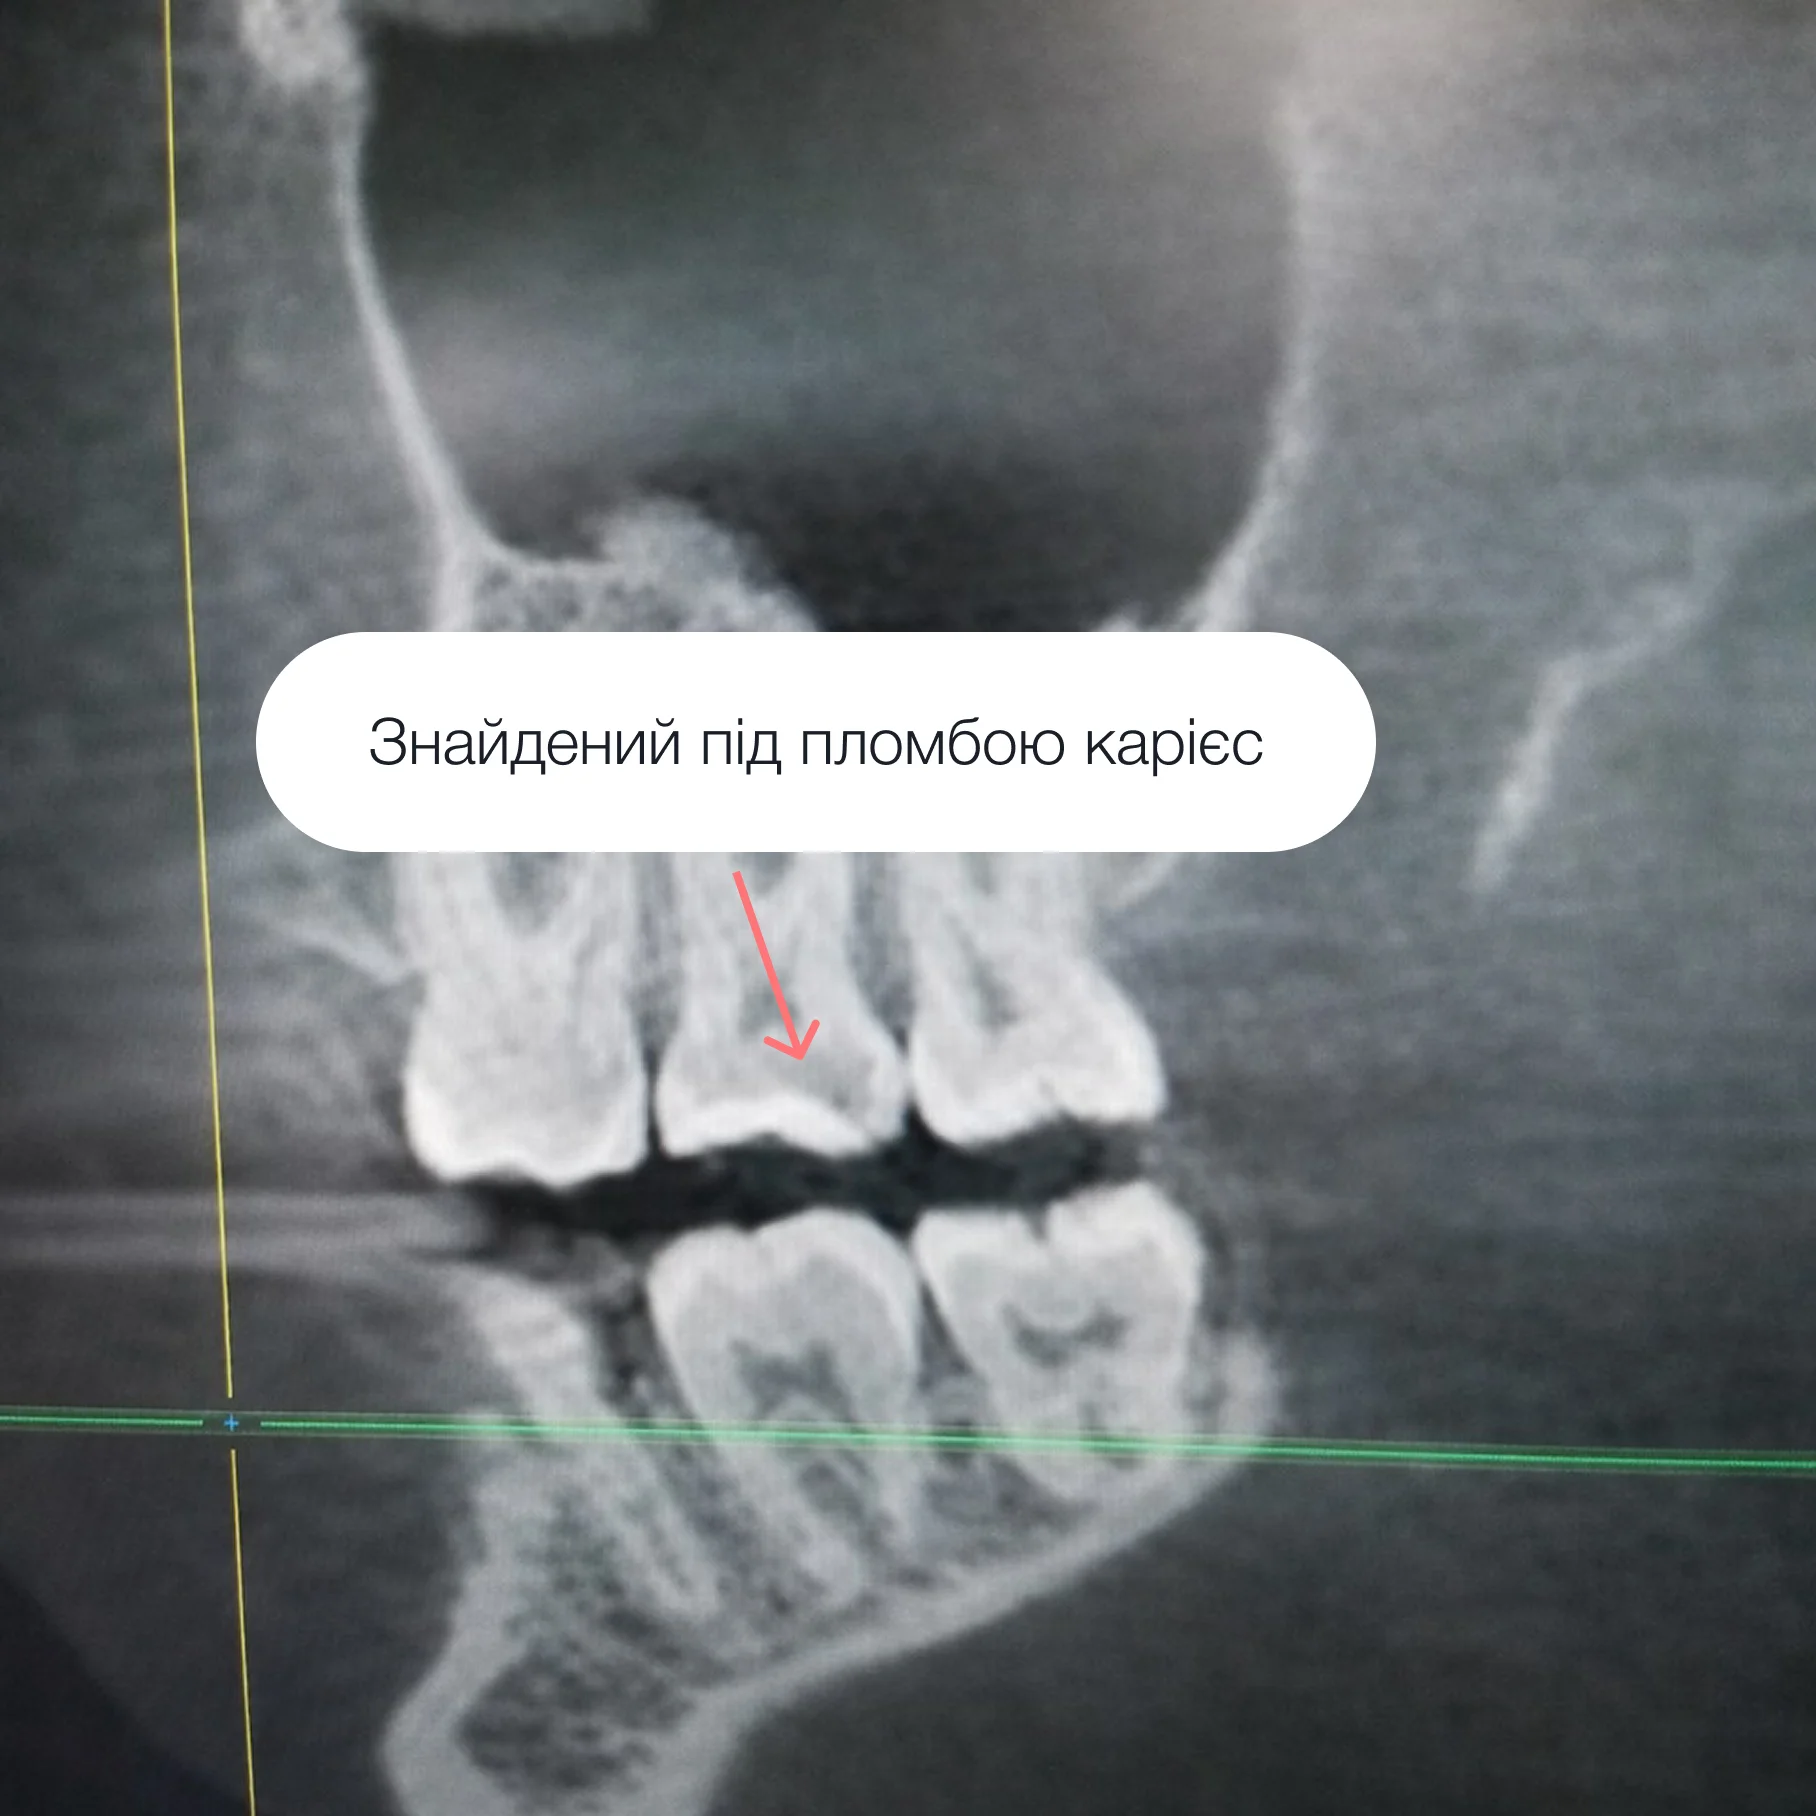

Карієс поширюється зсередини, і якщо почекати, ураження стане глибшим. Це може призвести до:

– лікування каналів,

– керамічних вкладок,

– коронок,

– значно дорожчого лікування.

Раннє втручання дозволяє повністю зберегти зуб і уникнути ускладнень.